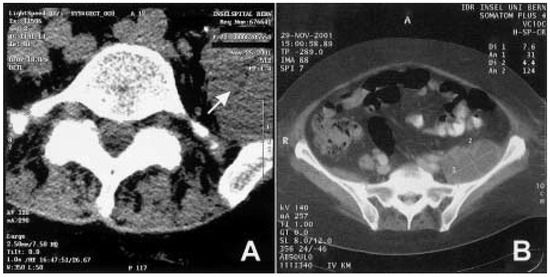

Infiziertes retroperitoneales Hämatom als ungewöhnliche Ursache eines Fallfusses

by R. H. Andres, Alain Barth and R. W. Seiler

Swiss Arch. Neurol. Psychiatry Psychother. 2004, 155(2), 60-63; https://doi.org/10.4414/sanp.2004.01460 - 1 Jan 2004

This is a case report of a 72-year-old woman under oral anticoagulation who presented in the emergency room with a subacute onset of left-accentuated lumboischialgia, a left-side foot drop, a foot plantar flexion palsy and an eversion weakness. Other clinical findings included an [...] Read more.

This is a case report of a 72-year-old woman under oral anticoagulation who presented in the emergency room with a subacute onset of left-accentuated lumboischialgia, a left-side foot drop, a foot plantar flexion palsy and an eversion weakness. Other clinical findings included an abscessing parotitis and an oligoarthritis of unknown aetiology. The neuroradiological evaluation with computer tomography and myeloradiculography did not show any adequate spinal or radicular affection. A complete left-leg palsy and increasing sensory deficits developed during the early course of the hospitalisation. A pelvic CT was performed and revealed a left-sided retroperitoneal mass lesion with compression of the sacral plexus and the ischiadic nerve. CT-guided puncture resulted in the diagnosis of a haematoma infected with Staphylococcus aureus. We considered this process to be induced by the anticoagulant treatment and secondary septic dissemination from the parotid abscess. Percutaneous drainage and antibiotic treatment resulted in fast clinical recovery of the motor deficits; however, mild sensory residues persisted. Our case report demonstrates the necessity to consider for possible extraspinal lesions also in patients presenting with the typical symptoms of radicular compression, particularly when the initial evaluations were not conclusive. Full article

Show Figures

Figure 1